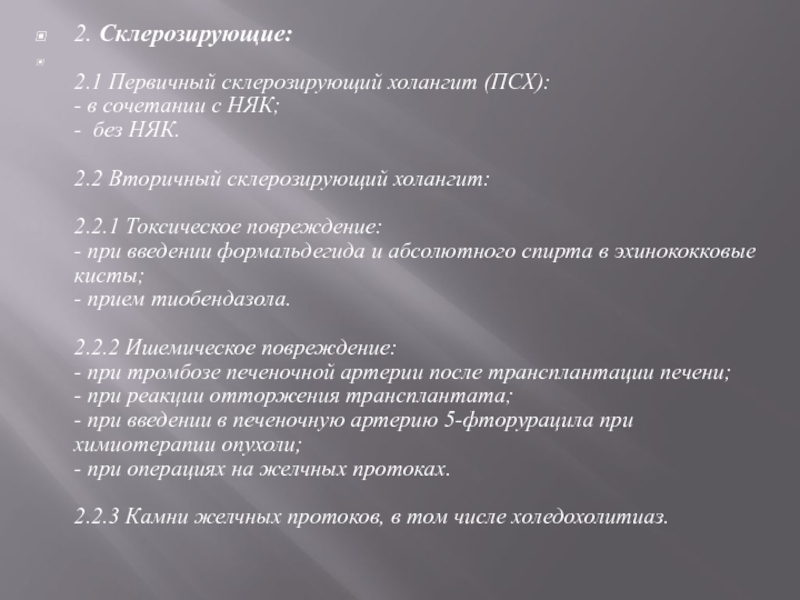

Фотографии и изображения, связанные с симптомами первичного склерозирующего холангита